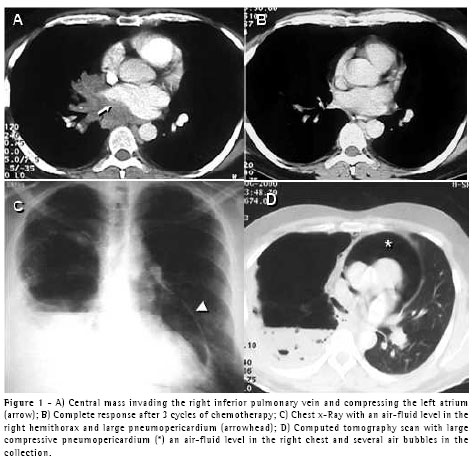

A 64-year-old male patient with chronic obstructive pulmonary disease was submitted for coronary artery bypass graft (CABG) with left internal mammary artery-left anterior descending anastomosis. In the intensive care unit, at two hours after extubation, he presented a spontaneous left-sided pneumothorax that was controlled through insertion of a 14FR pigtail catheter, after which the patient improved. Two days later, however, he presented respiratory discomfort and a second pneumothorax was seen despite the fact that the pigtail catheter remained in the pleural cavity and was unobstructed. A second pigtail catheter was inserted in an anterior position. The problem was resolved, and the catheters were removed. On the following day, the patient presented hypotension, tachycardia and dyspnea. For technical reasons, it was not possible to perform an echocardiogram. A CT scan showed an anterior left pneumothorax and a large pneumopericardium (Figure 2). A 32FR chest tube was inserted into the left pleural cavity, and the problem was completely resolved. The patient also underwent talc pleurodesis. The same simple solution (tube thoracostomy) was applied in this second case.